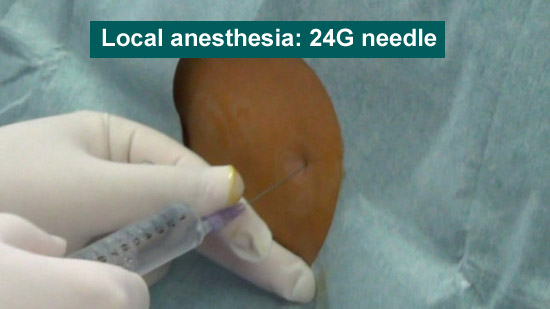

●Local anesthesia

24-gauge needle (Local anesthesia needle)

Local anesthetic

(1)Local anesthesia (24-gauge needle)